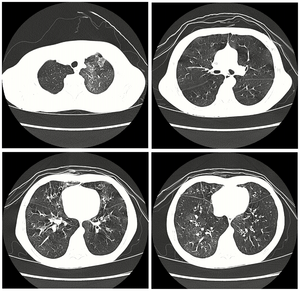

![]() | |

High resolution CT scan showing bronchiolitis obliterans with mosaic attentuation, bronchiectasis, air trapping and bronchial thickening[3] | |